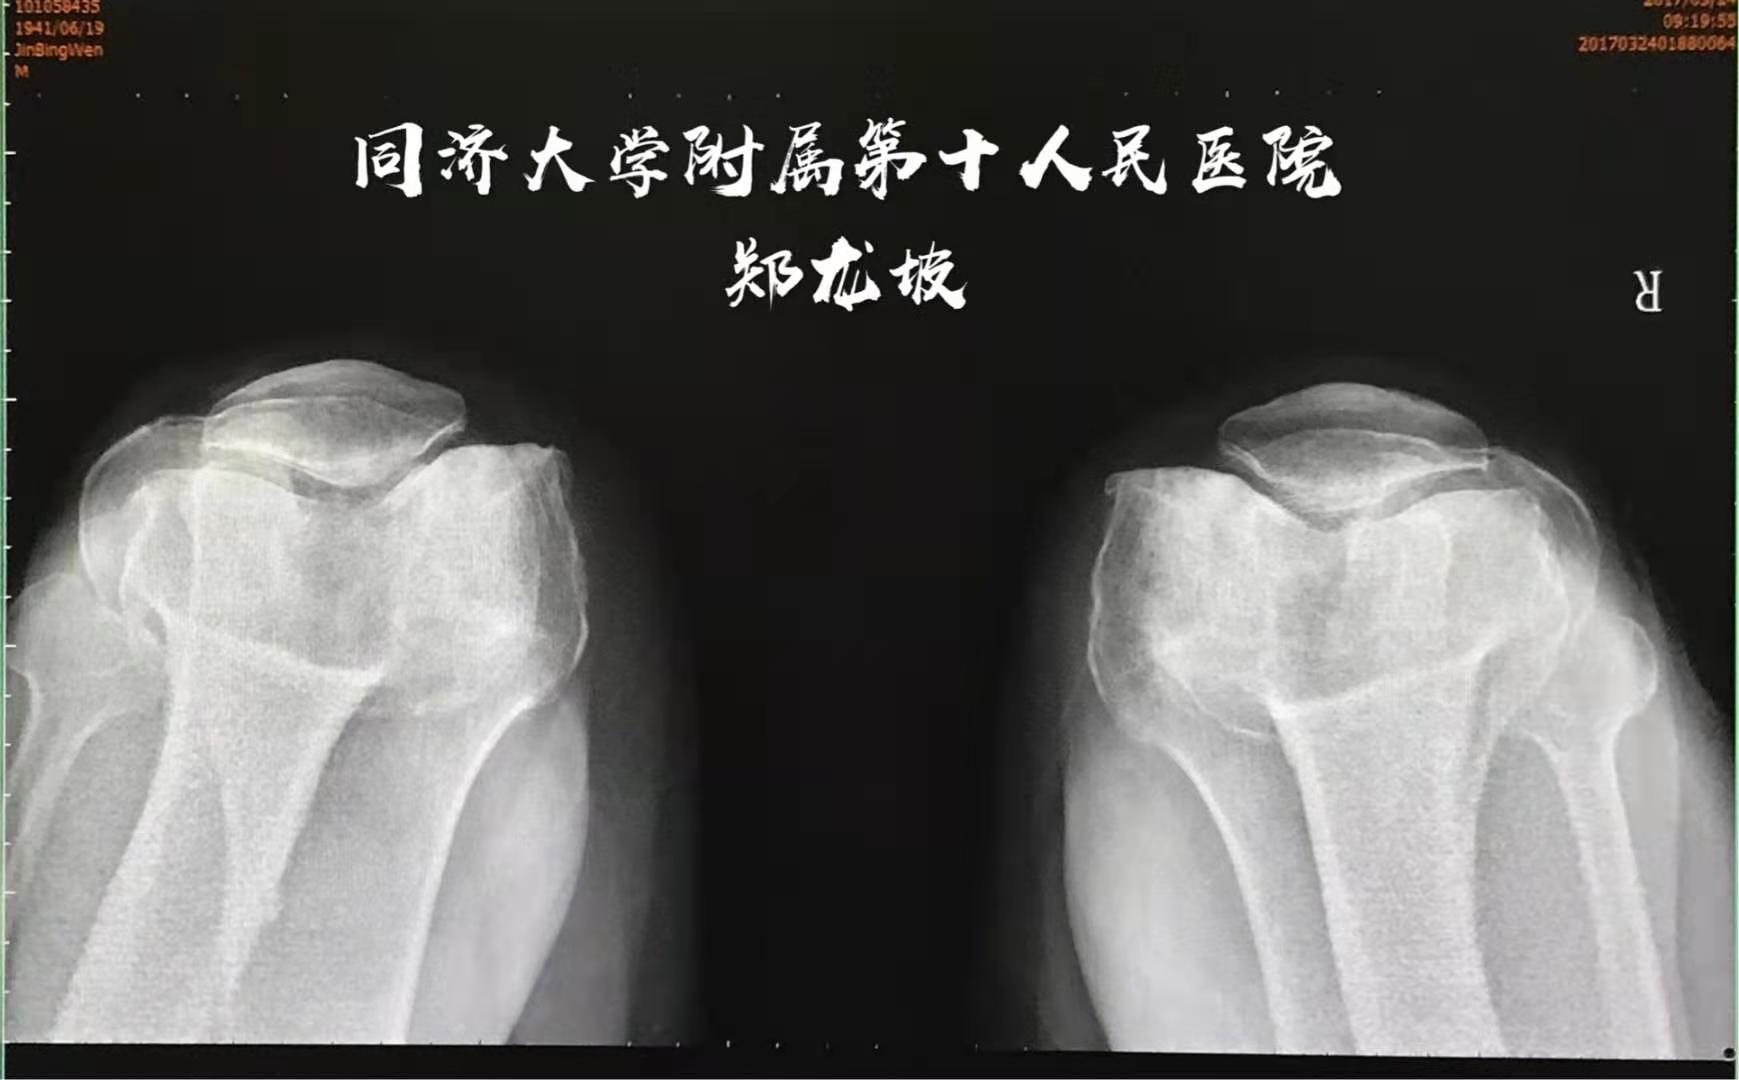

髌骨轴位片清晰显示髌骨关节磨损状况